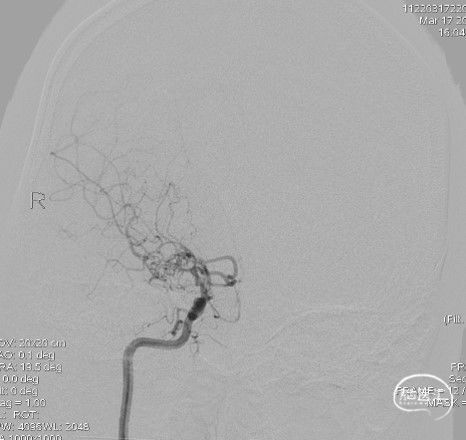

右侧颈内动脉侧位:

造影:右侧颈内动脉末端变细,大脑前及大脑中自起始部闭塞,脑底少量烟雾血管形成,汇聚使R-MCA少量分支显影。